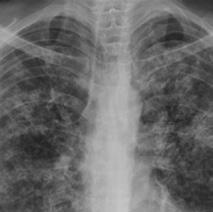

• Severe long-standing cough that produces phlegm

• Weight loss

• Night sweats

• Lung damage visible on imaging (e.g., infiltrates in lung on x-ray)